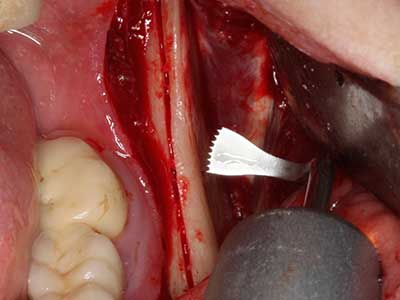

Quando le procedure chirurgiche vengono eseguite sull'osso nelle immediate vicinanze di strutture sensibili, come vasi sanguigni o nervi, gli strumenti rotanti pongono un rischio significativo di lesione iatrogena. I dispositivi piezoelettrici possono essere utili per la preparazione delle coperture ossee e la rimozione del tessuto duro in prossimità dei nervi, in particolare per la loro esposizione dopo una lesione iatrogena, ma anche durante la lateralizzazione dei nervi per le procedure di resezione e ricostruzione o il posizionamento di impianti (figg. 17-20). Il contatto leggero tra puntina piezoelettrica e nervo non causa generalmente danni, ma se si procede senza prestare attenzione con movimenti a sega o raccordi con residui di substrati ossei possono verificarsi danni al nervo temporanei o anche permanenti. Il rischio di danno, tuttavia, è considerato sostanzialmente inferiore al rischio presente utilizzando seghe o frese (Pereira, Gealh et al. 2014).

Indicazione: terapia parodontale